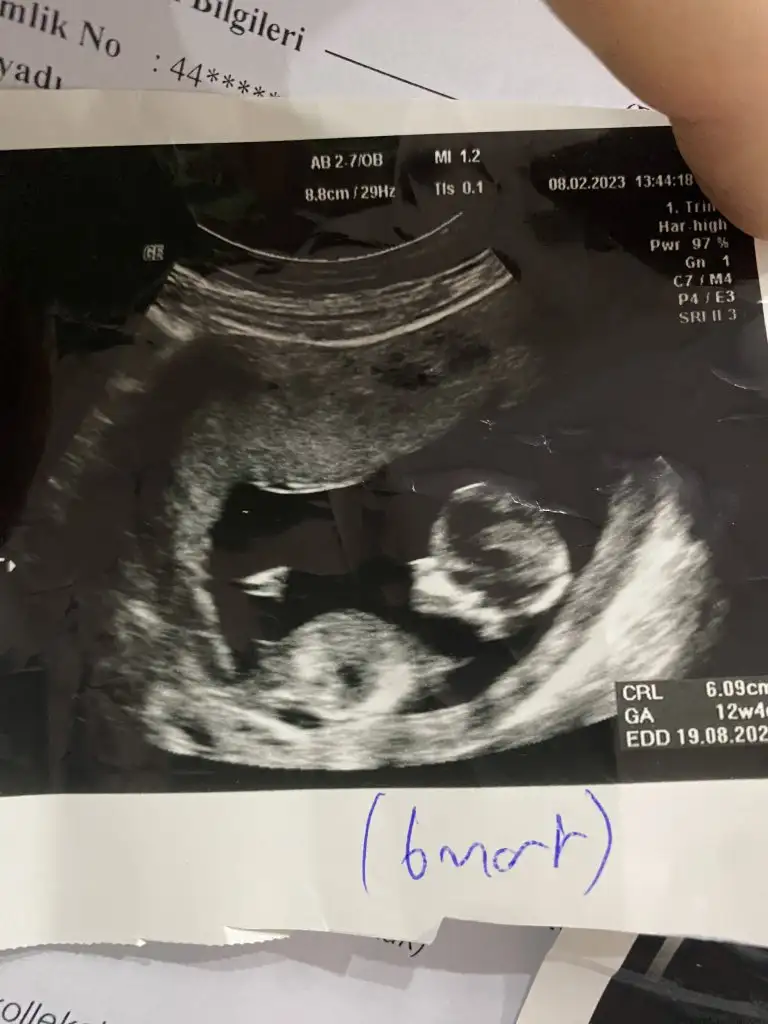

Merhabalar, benimde ultrason görüntülerime göre yorum yapabilecek var mı? ☺️ Şimdiden teşekkürler 🤲